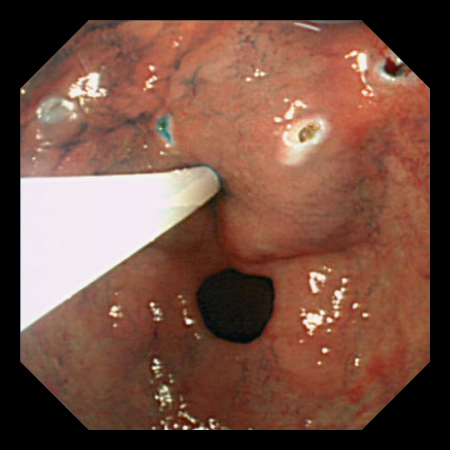

EST

起始火花監測

透過偵測放電量,控制高周波電壓輸出,以確保火花(電弧)處於最低限度的功能,減輕切割時對組織的過度侵犯和炭化。對於肌肉和脂肪等特性不同的組織,能實現一致性的切割。